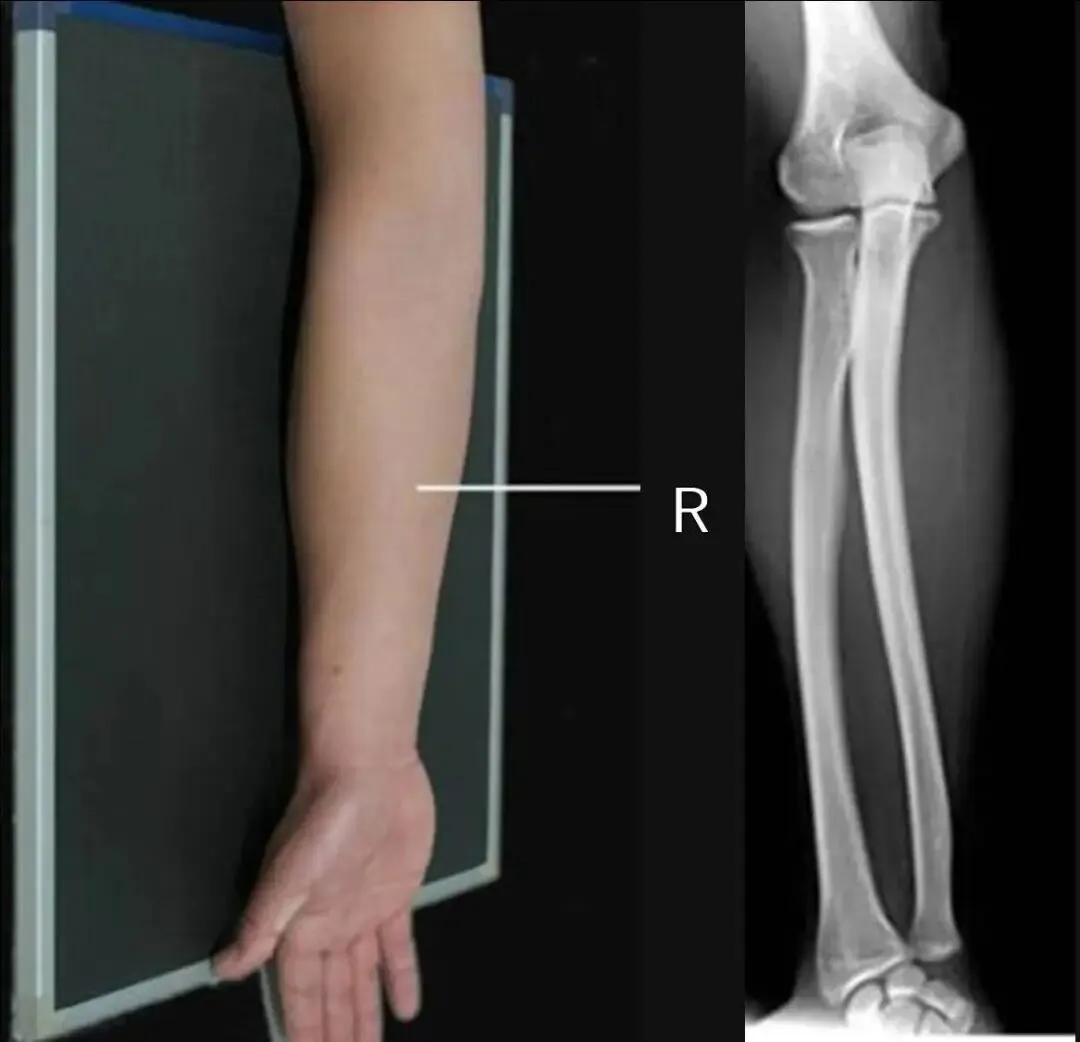

一、先来看几组图片

四、桡尺骨正位

1.摄影要点:

(1)受检者面向摄影台就坐,前臂伸直,掌心向上,背面贴近摄影台面,前臂长轴与探测器长轴平行;

(2)照射野和探测器上缘包括肘关节,下缘包括腕关节;

(3)源-像距离为100cm;

(4)中心线对准前臂中点,垂直射入探测器。

2.桡尺骨正位标准影像显示:

(1)显示桡、尺骨正位影像;

(2)腕关节和(或)肘关节呈正位像显示;

(3)诸骨纹理及周围软组织清晰可见。